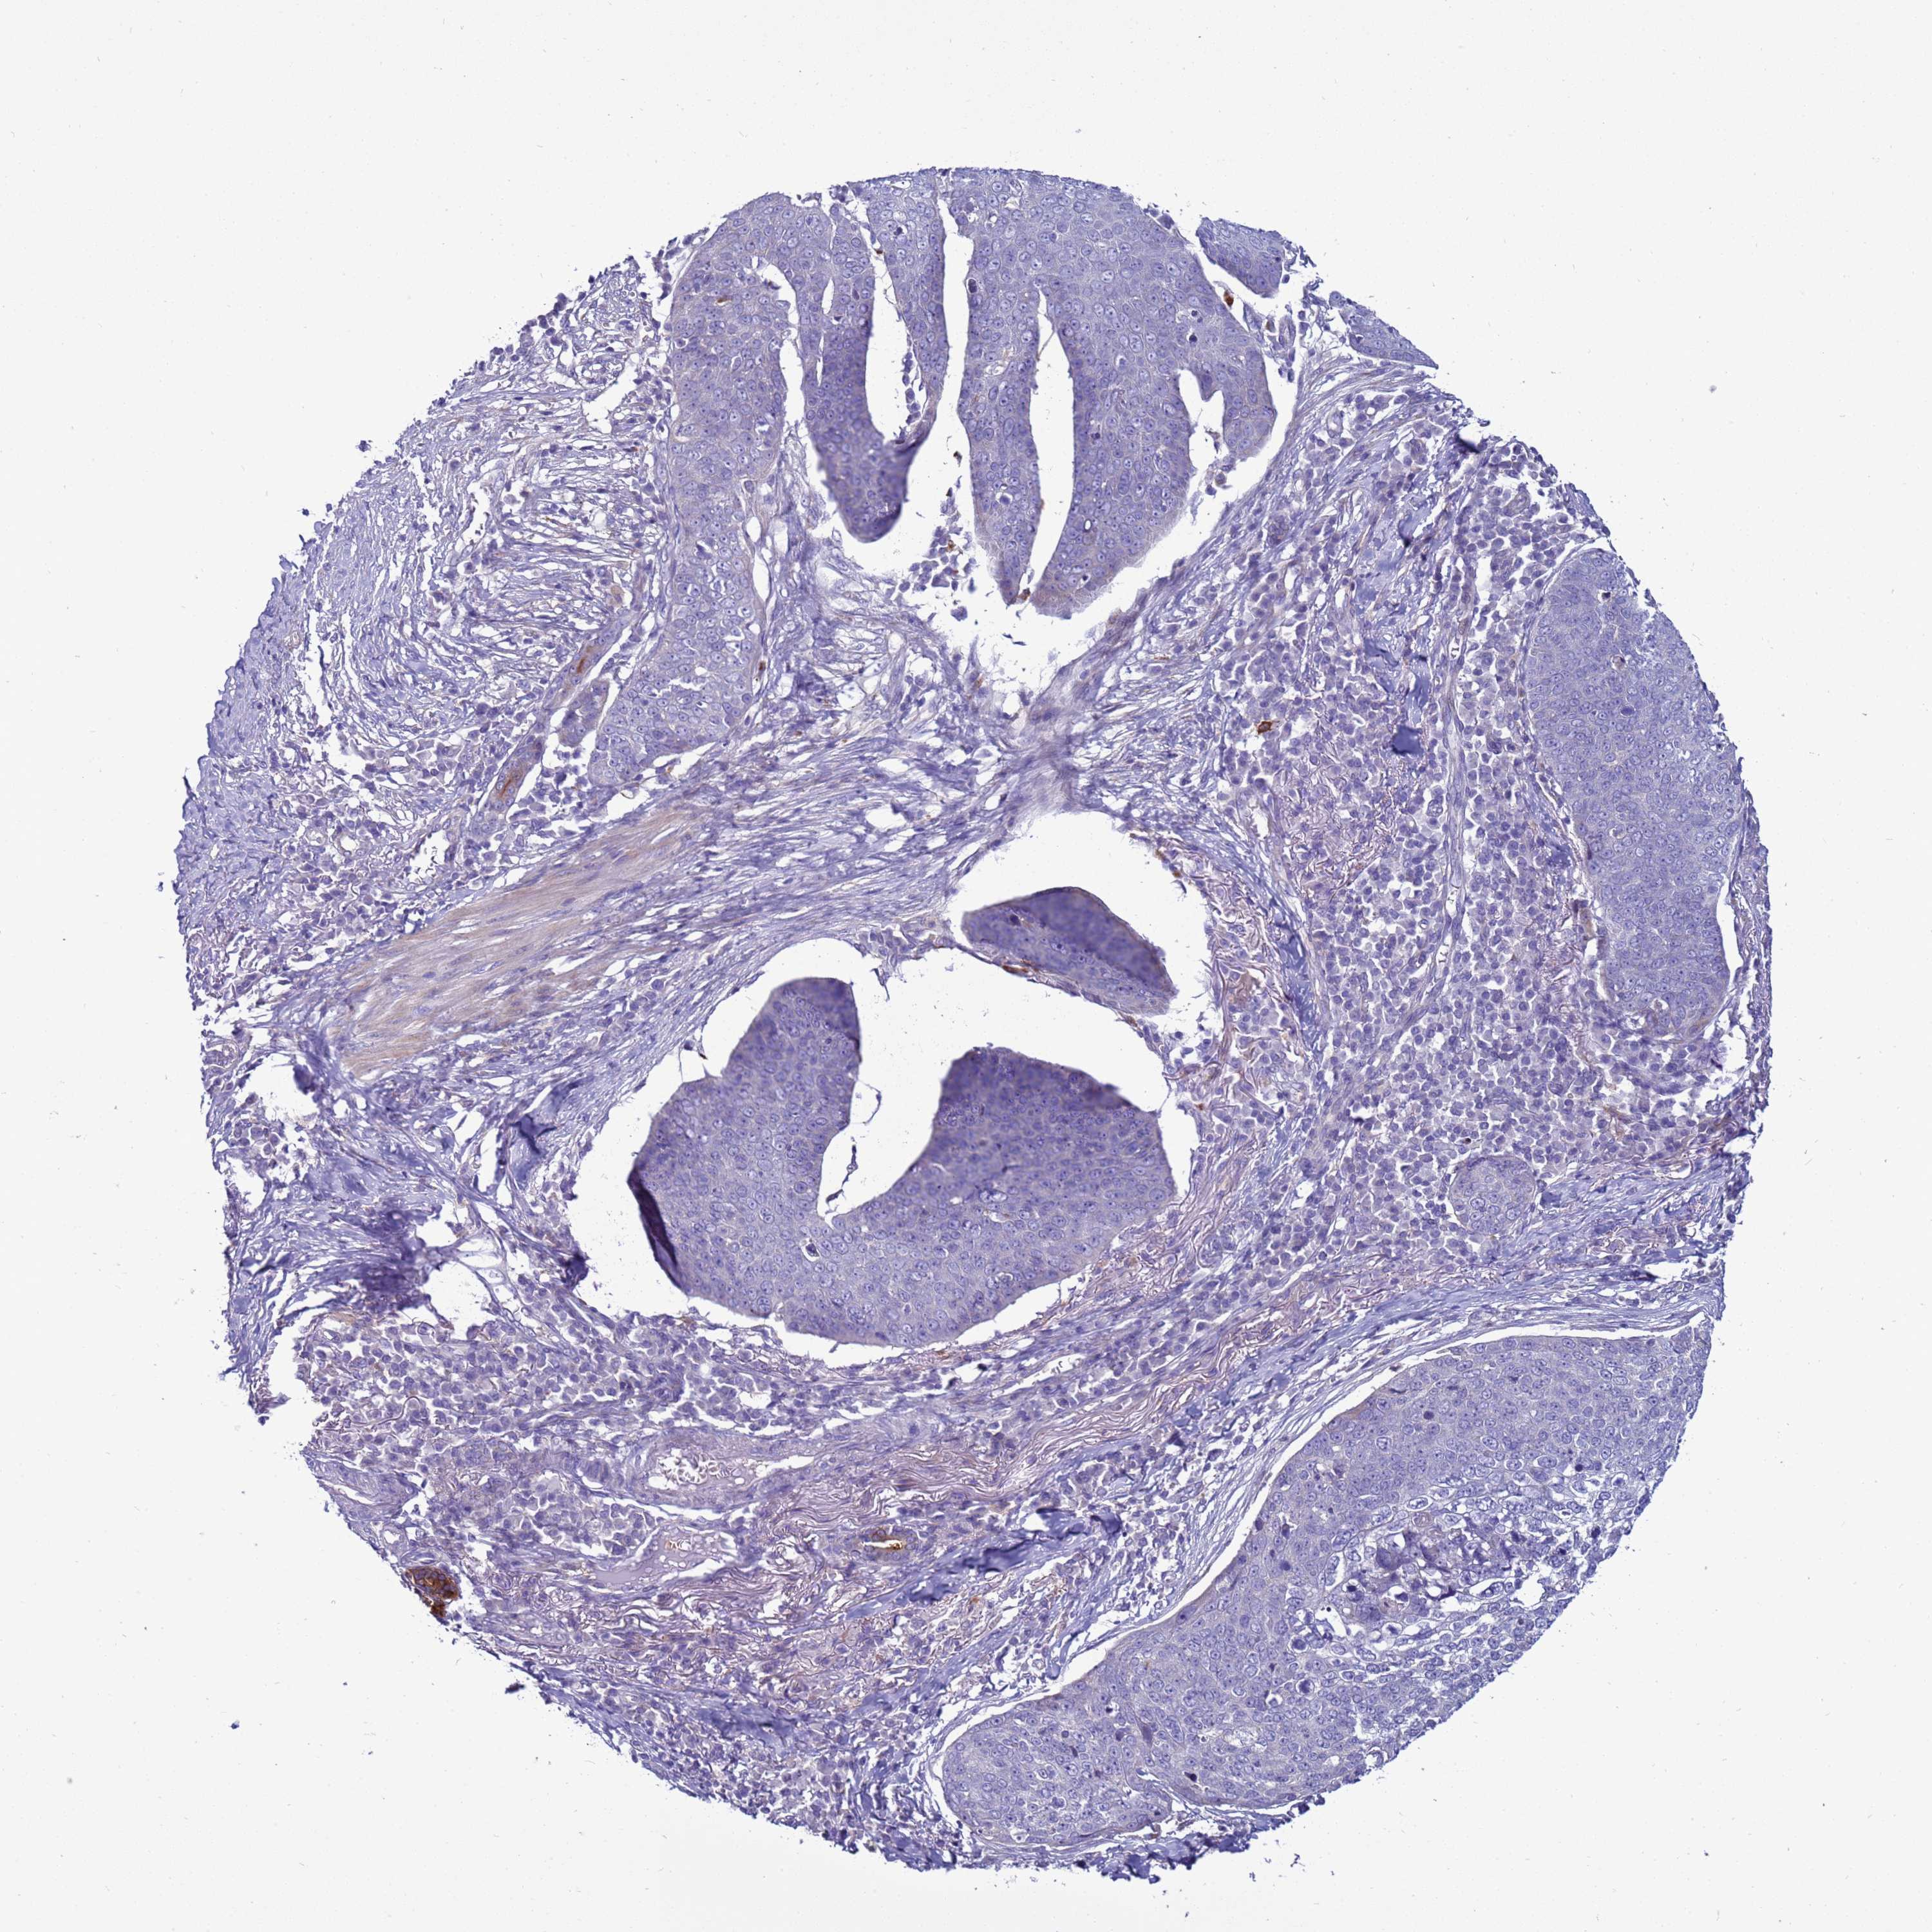

SKIN CANCER - Protein expressioni

A mouse-over function shows sample information and annotation data. Click on an image to view it in a full screen mode. Samples can be filtered based on level of antibody staining by selecting one or several of the following categories: high, medium, low and not detected. The assay and annotation is described here.

Antibody stainingi

Antibody staining in the annotated cell types in the current human tissue is reported as not detected, low, medium, or high, based on conventional immunohistochemistry profiling in selected tissues. This score is based on the combination of the staining intensity and fraction of stained cells.

Each image is clickable and will lead to virtual microscopy that enables deeper exploration of all samples and also displays staining intensity scores, fraction scores and subcellular localization as well as patient and tissue information for each sample.

Antibody HPA043704

Squamous cell carcinoma, metastatic, NOS